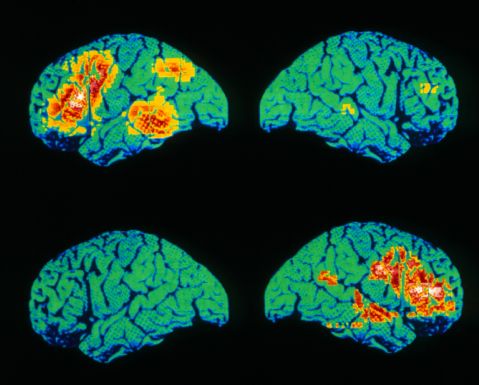

Mail-order house for left-hander Schoolboy Writing with Chewed-Up Pencil Stub Woman Writing akg188502 C0115766-Boxing_pose,_X-ray-SPL File photo of Phil Mickelson at Pebble Beach Spanish tennis player Nadal attends a training session at country club Las Salinas in Vina del Mar City Left and right handed scissors on red fabri Executive signing a contract Therapist teaching stroke patient to write Colour PET scan of language areas of the brain